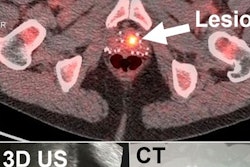

T2-weighted fast spin-echo MRI (A), F-18 choline PET (B), and fused PET/MRI (C) show a 0.68-cm3 left anterior transitional zone lesion that was confirmed on targeted biopsy. A magnified view of PET/MRI (D) shows a target lesion (magenta) and respective mirrored (blue) background volumes of interest. Image courtesy of JNM.A total of 52 lesions were detected by multiparametric MRI (19 low, 18 intermediate, and 15 high-risk), and mpMRI-assigned risk was a strong predictor of final pathology (area under the curve [AUC] = 0.81, p < 0.001).

Using the mean F-18 choline target-to-background ratio, the addition of F-18 choline to mpMRI significantly improved the prediction of significant cancers, compared with mpMRI alone (AUC = 0.92, p < 0.001).